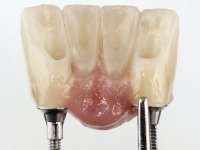

Após estudo imagiológico foi planificada a colocação de dois implantes de 3.3 mm de diâmetro e 10 mm de comprimento. No dia da cirurgia foram extraídos os dentes 42 e 32 e removido o implante. Os implantes foram colocados na zona dos alvéolos tendo o cuidado de lingualizar um pouco o seu posicionamento. Foi feita uma impressão pela técnica de moldeira aberta com o retalho aberto para a confeção da ponte provisória imediata. Enquanto a impressão foi para o laboratório, foram colocados parafusos de cicatrização altos e feita a sutura da ferida cirúrgica. A paciente esperou 2 horas na sala de espera enquanto no laboratório era confecionada a ponte provisória. A ponte provisória imediata aparafusada foi colocada e o seu assentamento controlado imagiologicmente. Passados 3 meses foi realizada a impressão definitiva com uma técnica de moldeira aberta. Nessa consulta aproveitamos para polir a ponte provisória com taças de borracha para que os tecidos moles pudessem maturar em melhores condições. Foi feita a recolha de informação para caracterizar da melhor forma a estrutura monolítica em Zr. Foram utilizadas guias de cor para a cerâmica de tonalidade coronária e gengival. No laboratório foi confecionada uma ponte em Zr. aparafusada que foi cuidadosamente caracterizada. Após aprovação pela paciente foi colocada definitivamente em boca. O aperto foi feito com uma chave dinâmica com 35 N de torque. Os orifícios foram tapados com teflon e obturados com resina composta.